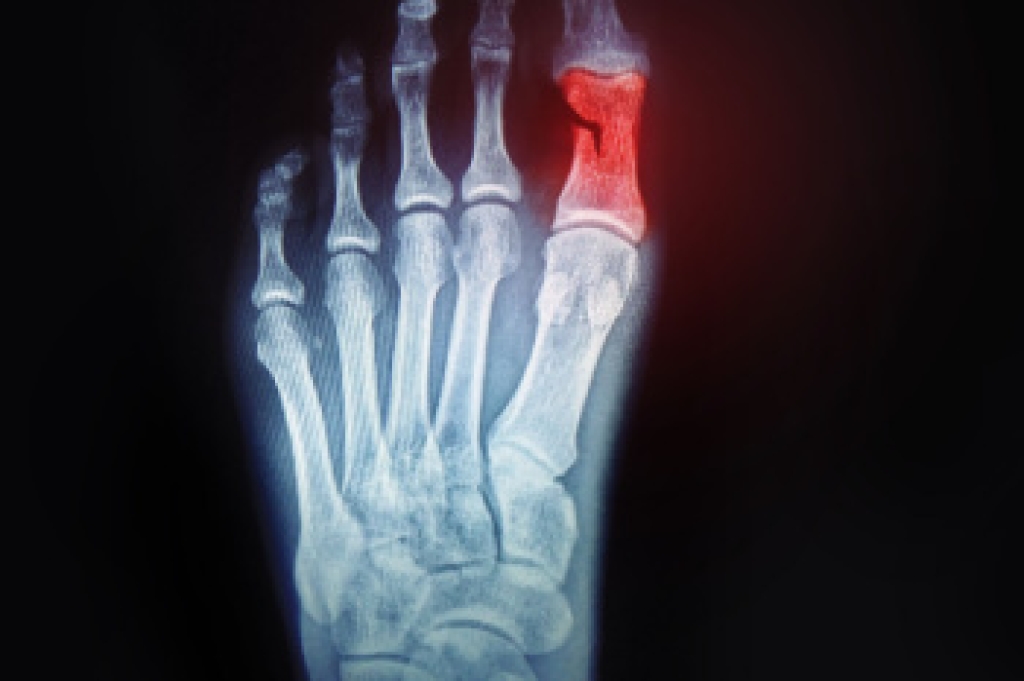

Stress fractures occur when there is a tiny crack within a bone. To learn more, contact James P. Huish, DPM from Arizona. Our doctors can provide the care you need to keep you pain free and on your feet.

Stress fractures are the result of repetitive force being placed on the bone. Since the lower leg and feet often carry most of the body’s weight, stress fractures are likely to occur in these areas. If you rush into a new exercise, you are more likely to develop a stress fracture since you are starting too much, too soon. Pain resulting from stress fractures may go unnoticed at first, however it may start to worsen over time.

Stress fractures do not always heal properly, so it is important that you seek help from a podiatrist if you suspect you may have one. Ignoring your stress fracture may cause it to worsen, and you may develop chronic pain as well as additional fractures.